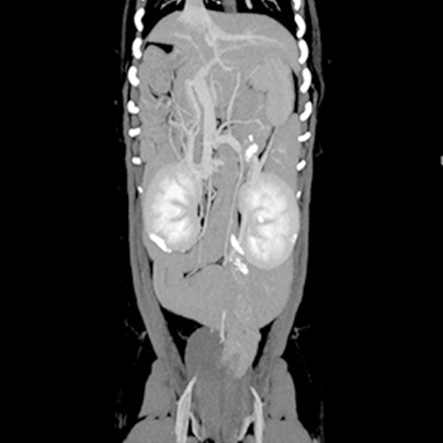

CT検査により、通常の画像検査では検出しにくい病気の早期発見・診断につながる可能性が高まります。

CT画像の検査・読影のみも受け付けております。